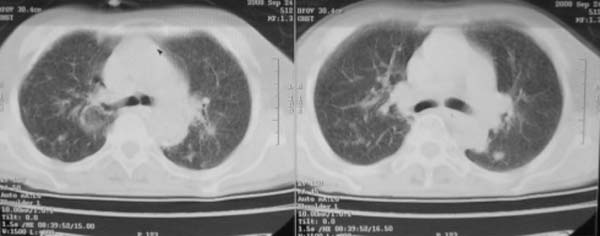

女,78岁,声嘶月余,否认有既往病史,有粉尘接触史10年。

双上肺结节融合影,周围有纤维条索影,结合粉尘接触史,首先考虑尘肺。双侧颈部有增大淋巴结,有声嘶表现,肺癌淋巴结转移不能排除。可结合颈部淋巴结活检。